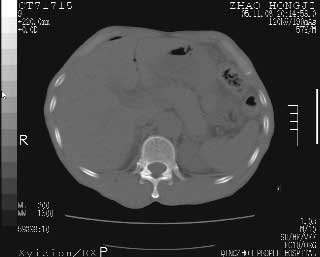

临床资料:男性,57岁,上腹部疼痛并5天,突然加重并延及全腹伴恶心5小时入院。胰淀粉酶化验在正常范围。检查:腹肌紧张,全腹压痛、反跳痛,尤以右上腹部为著。肠鸣音减低。血常规:wbc14.6x10/9, n:11.3x10/9 ,血压:135/90mmhg. 胸部透视:腹部肠腔轻度张气,未见其它异常改变。

从图提示我同意空腔脏器穿孔的诊断,来源肠道{由于病程较短,故没能见到肠系膜聚局的征象}。

肝缘见少许气体,胰尾部见少许气体包饶(蓝色圈),12指肠上部或球部邻近胆囊周边也可见少许气体影(黄色圈),并忖托出胆囊壁,12指肠远段肠道内未见明显气体(白色箭)。

肝脏前缘见少量积气、胰尾部见少许气体包饶,肾前筋膜未见增厚,临床淀粉酶不高,意见:上消化道穿孔。

消化道穿孔。12指肠球部周和胰周积气考虑12指肠穿孔可能性大。

腹腔内脂肪影密度增高,考虑腹膜炎

入院3小时后行剖腹探查术,见腹腔内大量脓性混浊液约1000ml,十二指肠球部溃疡穿孔,溃疡面约2.5x2cm,穿孔直径约0.6cm。胃内容物外益,周围组织炎性水肿明显。行十二指肠穿孔修补术。术后诊断:

1、十二指肠溃疡穿孔

2、弥漫性腹膜炎

对于少量的腹腔游离气体,ct检查较普通透视有绝对的优势,它不仅可以看到肝脏前上缘的气体,而且还能够看到小网膜区的游离气体。从而可以肯定诊断。各位分析战友的很好,感谢大家的参入!